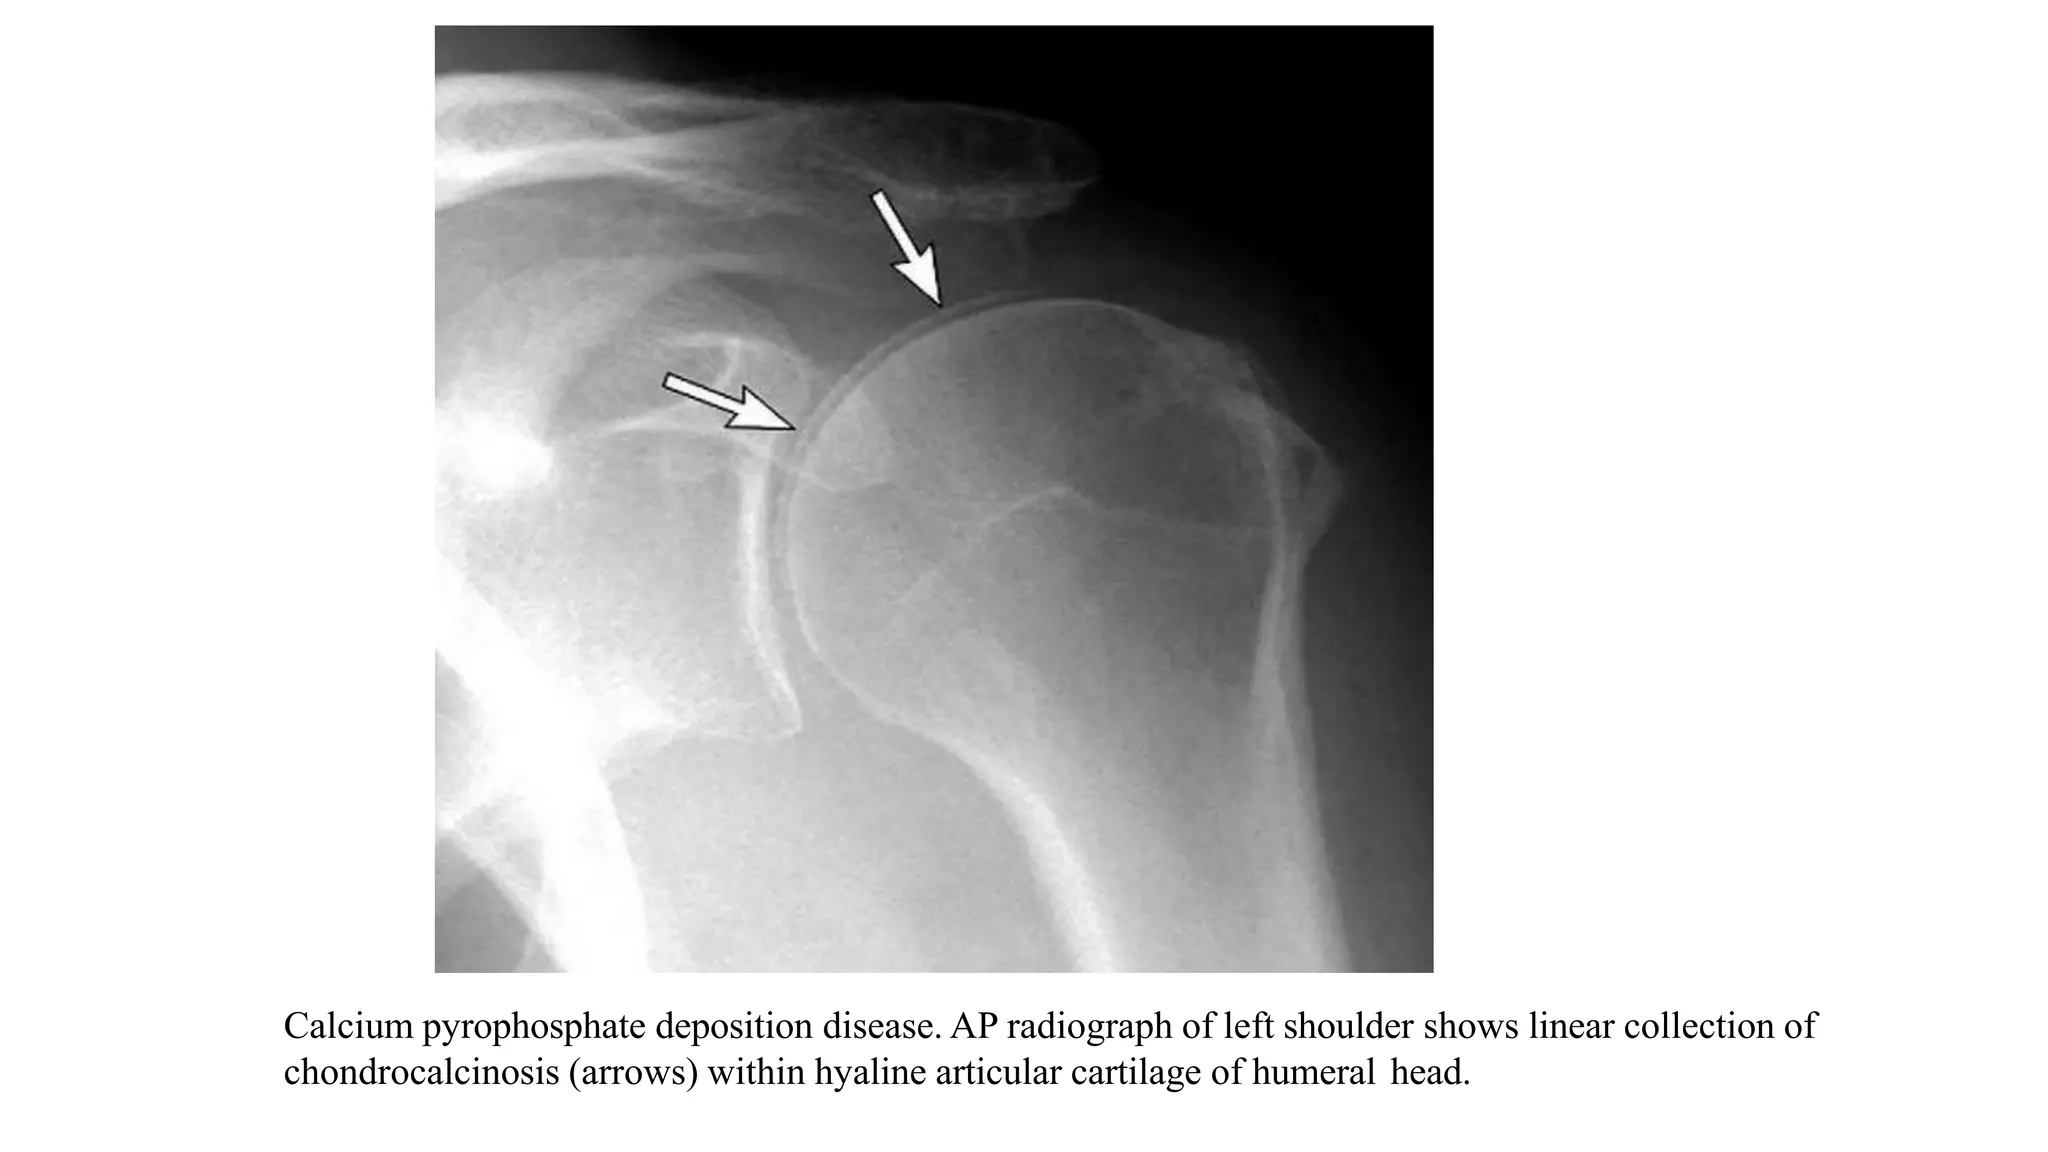

3. CPPD DEPOSITION DISEASE

• Calcium pyrophosphate dihydrate deposition is a crystal deposition arthropathy that results from

deposition of CPPD crystals into the hyaline cartilage, labrum, and other soft-tissue structures of the

shoulder.

• Radiographically, this results in the hallmark finding of chondrocalcinosis, which is not as common

within the shoulder as it is in the knee or wrist.

• Over time, CPPD results in secondary osteoarthritis of the glenohumeral joint.

• With the exception of prior trauma, CPPD is the leading cause of secondary osteoarthritis in the shoulder,

especially if the OA is bilateral.

Calcium pyrophosphate deposition disease. AP radiograph of left shoulder shows linear collection of

chondrocalcinosis (arrows) within hyaline articular cartilage of humeral head.